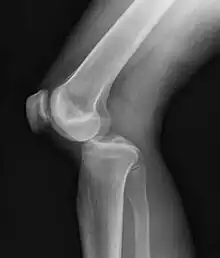

Plain X-rays, CT scan, ultrasonography, or MRI may help with the diagnosis.[2][11] Findings on X-ray that may be useful among those who have already reduced include a variable joint space, subluxation of the joint, or a Segond fracture.[5]